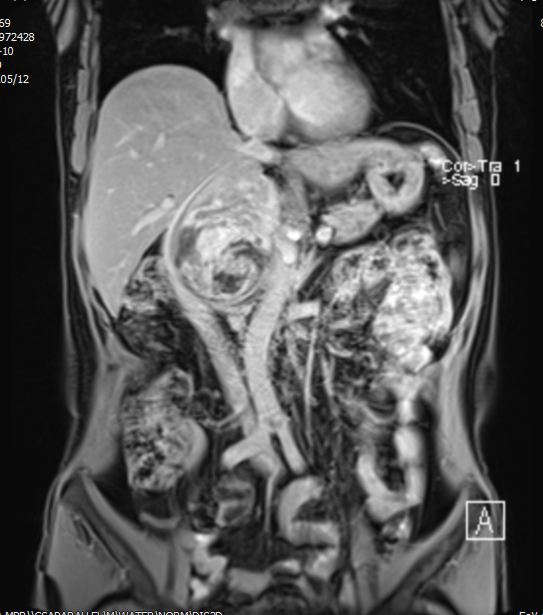

患者一,女性,62岁。因“体检发现右侧肾上腺区占位10余天”入院。入院后完善相关检查及化验,其中RAAS系统化验正常,尿液中香草扁桃酸及游离肾上腺素升高3倍,CT提示右侧肾上腺区混杂密度占位性病变,内可见结节状钙化灶,大小约129*97*98mm,下腔静脉受压向前向外侧偏移,邻近脏器受压改变,增强扫描未见明显不均匀强化。MR显示右侧肾上腺区占位病变,合并囊性变、坏死、出血,多考虑恶性肿瘤性病变,嗜铬细胞瘤恶变多考虑并右肾动静脉、下腔静脉、邻近脏器受压移位,胸部CT及全身骨显像未见明显转移灶,术前诊断为腹膜后肿瘤。泌尿外科在充分做好术前准备后,为患者实施开放腹膜后肿瘤切除术,最终完整切除肿瘤及肾上腺,手术历时约3小时,患者术后恢复良好,术后病检提示嗜铬细胞瘤。